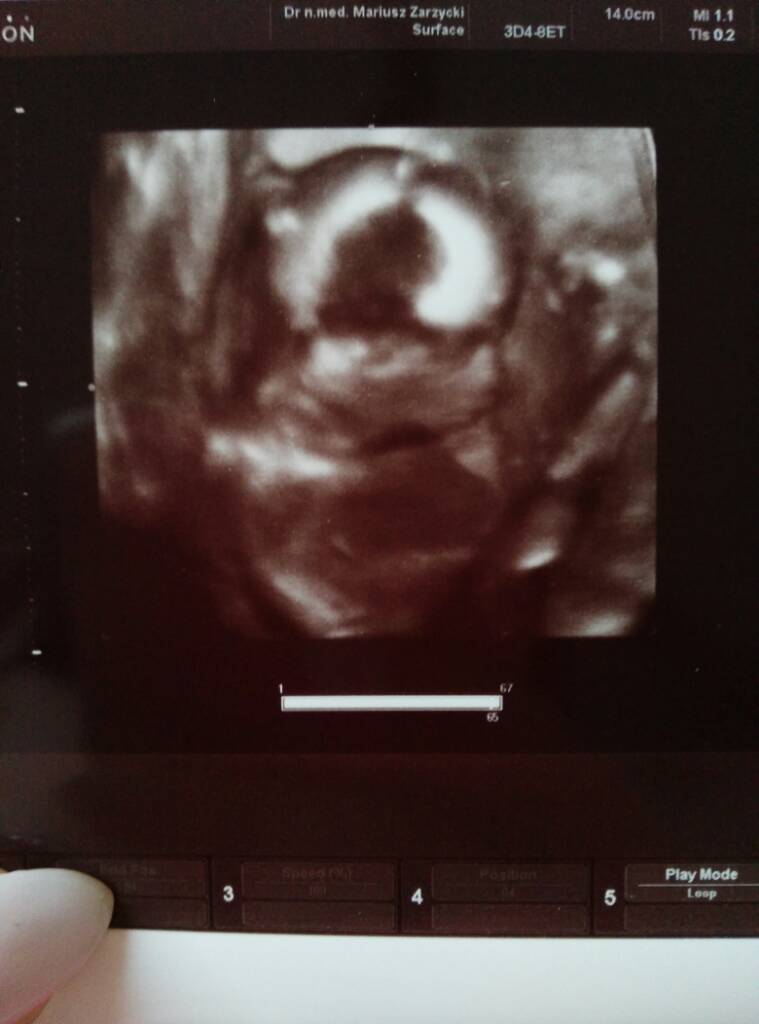

No i zdjęcie oczywiście. Jak ładnie ssie kciuka ale dalej nie wiemy kto to :p

uploadfromtaptalk1464975399394.jpg